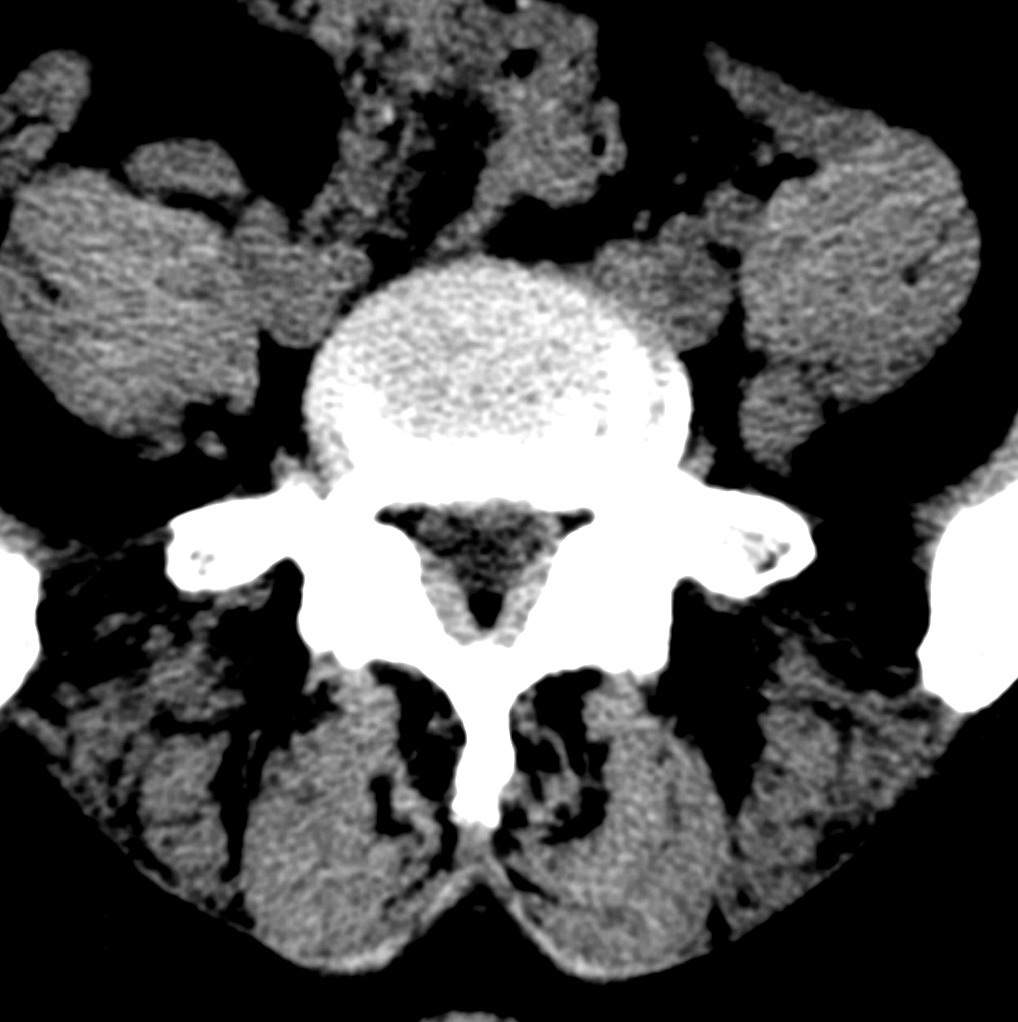

标题: CT19570:是否为腰脱? [打印本页]

标题: CT19570:是否为腰脱?

可以定腰脱否?

大于椎体的环状软组织影,椎间盘膨出

椎间盘膨出伴突出

支持间盘膨出伴突出。

双边征,考虑滑脱。

椎间盘突出

腰脱证据不足。

椎间盘膨出伴突出!

椎间盘突出,

椎间盘改变并不是很明显,黄韧带似乎有肥厚,